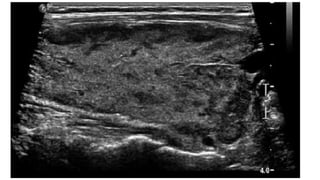

US image of a thyroid nodule (arrowheads) containing multiple fine punctuate echogenicity's

(arrow) with no comet-tail artifact, indicating high suspicion for malignancy. FNA and surgery confirmed PTC. (Reproduced from Frates MC.

Management of thyroid nodules detected at US: Society of Radiologists in Ultrasound consensus conference statement. Radiology2005;237:794–800;

with permission.)